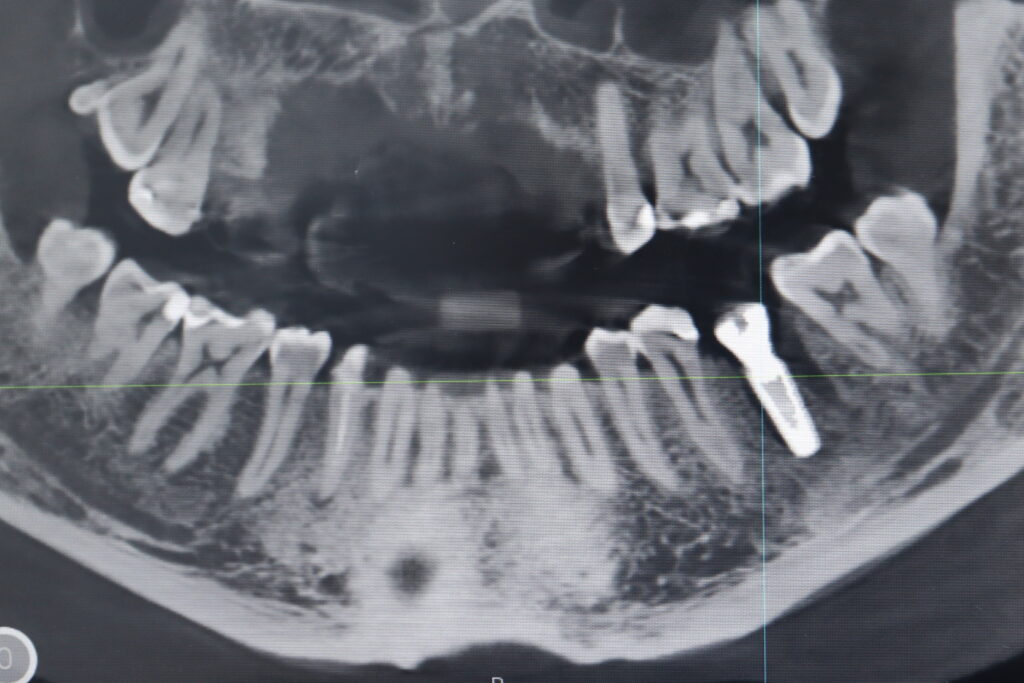

пациент до имплантации